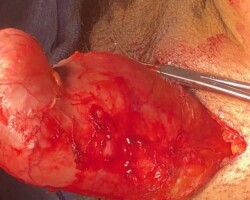

Resection of large retroperitoneal sarcoma including right and transverse colectomy and right hepatectomy